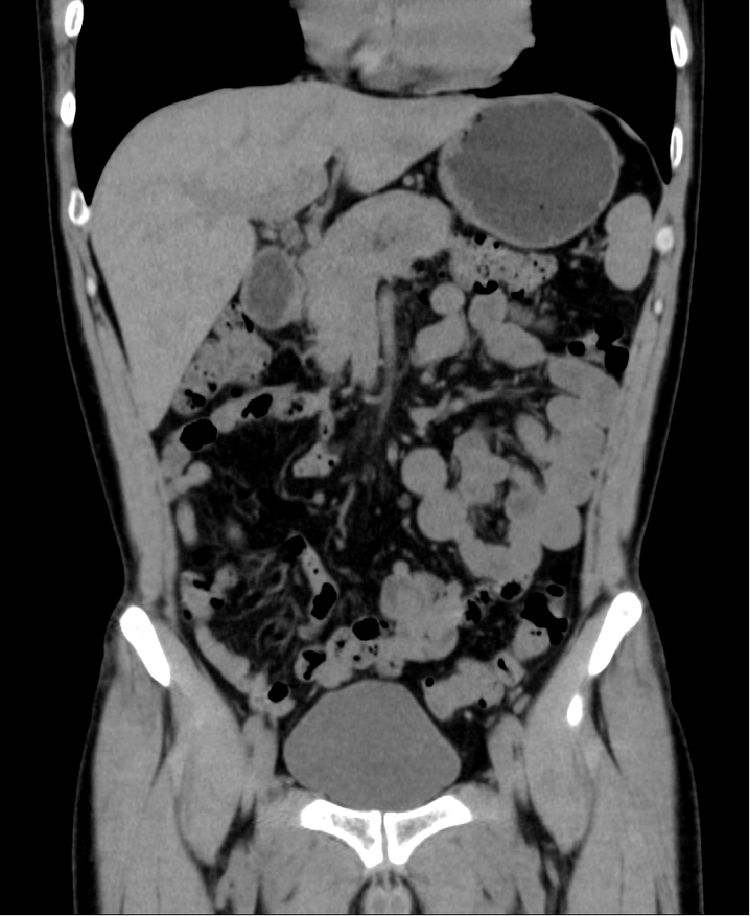

我院最新引进上海联影医疗研发生产的高端螺旋CT扫描系统,搭载量身定做的大热容量球管和超敏探测器,具备卓越的影像链。椎束重建技术实现立体等像素成像,还原真实高清影像,清晰呈现病灶细节;创新的工作流程大幅缩短患者等待时间;全新迭代技术大幅降低辐射剂量,实现安全绿色扫描。

CT图像具有密度分辨率高、组织结构无重叠等特点,有利于病变的定位、定性诊断,在疾病的诊断、治疗方案的确定、疗效观察和愈后具有重要的价值。尤其对脑血管病、肺结节筛查、腹部肿瘤的诊断价值明显,是目前常用的影像诊断和体检设备。

Real 3D椎束重建算法,提供高分辨率图像,实现“立体等像素”高清成像。

KARL 3D™ 双域迭代降噪技术,保证图像质量,有效降低60%辐射剂量。

精细骨骼显示,精准三维立体成像,细节一览无余。